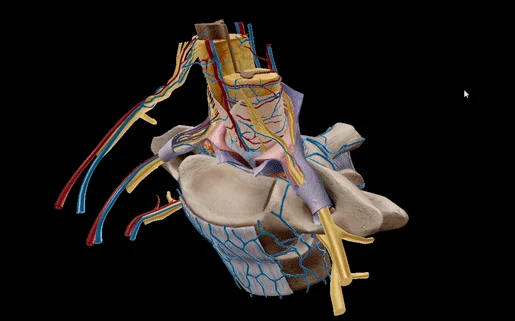

— Our Services

We Provide Exclusive Service